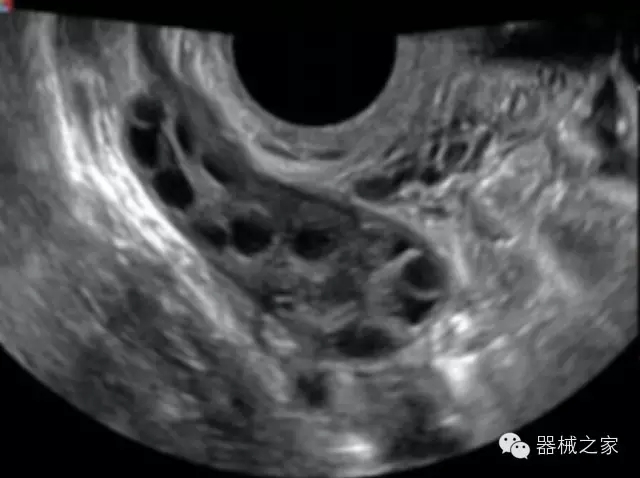

臨床圖片賞析

·獨(dú)有的大角度及實(shí)時(shí)溫控技術(shù),能同一切面顯示宮頸及宮體,有效減低了患者的痛苦,及保護(hù)粘膜保證了醫(yī)療安全;